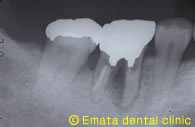

右下の奥歯が経過が悪く、腫れたりするので抜歯と診断しました。反対側に不必要な親知らずがありますので、移植を行いました。

移植後3年の状態です。奥から2番目の歯が移植した歯です。何の違和感もなく噛めています。

移植後3年のレントゲン写真です。良好な状態を維持しています。